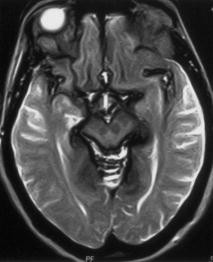

- Neurologische Störungen: Eine Eisenablagerung im Gehirn kann zu neurologischen Problemen führen, wie beispielsweise Gedächtnisverlust, Konzentrationsstörungen, Schwindel, Koordinationsproblemen und Muskelzuckungen.

- Bildgebende Verfahren: Bildgebende Verfahren wie Magnetresonanztomographie (MRT) oder Computertomographie (CT) können verwendet werden, um die Anwesenheit von Eisenablagerungen in den Geweben und Organen sichtbar zu machen.